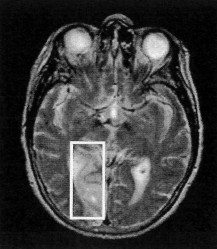

Document 2 : IRM du cerveau de la patiente réalisée

à la demande de l'ophtalmologiste après l'accident

Compte-rendu : "On note une importante atteinte dans la partie

postérieure et interne de l'hémisphère gauche

(zone encadrée)."

L'IRM confirme une lésion cérébrale dans

l'hémisphère gauche, ce qui explique les troubles dans

le champ visuel droit étant donné le croisement des

nerfs optiques des champs centraux de chaque il au niveau du

chiasma optique. L'aire cérébrale atteinte est la zone

V4 gauche qui doit être impliquée directement dans le

traitement des couleurs.